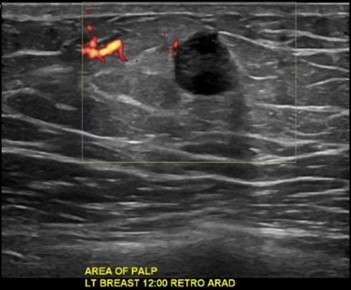

Invasive Ductal Carcinoma

Typically, ultrasound demonstrates a solid, hypoechoic mass. An eccentric location relative to the nipple can be a helpful distinguishing feature from gynecomastia1.